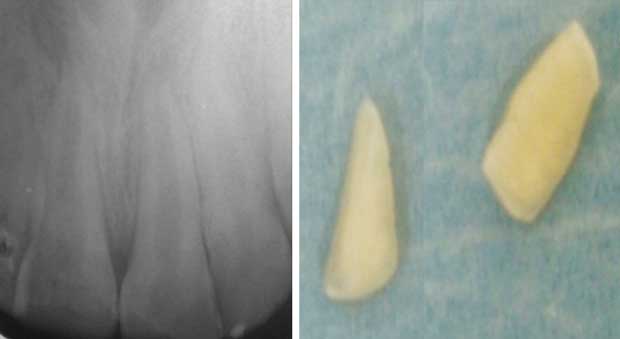

![]() Fig 10 : Rétro alvéolaire des dents concernées par le traumatisme et les deux fragments coronaires.

|

Cas clinique 2 :

Quinze heures après la survenue d’un traumatisme bucco-dentaire, une fille âgée de 9 ans s’est présentée aux urgences du CCTD de Casablanca. Une fracture coronaire amélo dentinaire au niveau de la 21 et une fracture coronaire compliquée sur la 11 ont été décelées lors de l’examen clinique. L’examen radiographique a montré l’immaturité radiculaire des deux dents.

Le collage des fragments dentaires par la technique simple a été réalisé après pulpotomie partielle sur la 11.

Les figures 9 à 13 montrent le traitement réalisé.